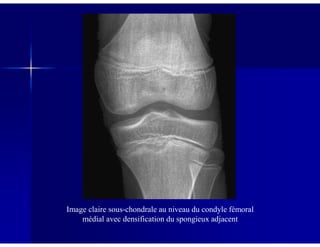

Image claire sous-chondrale au niveau du condyle fémoral

médial avec densification du spongieux adjacent